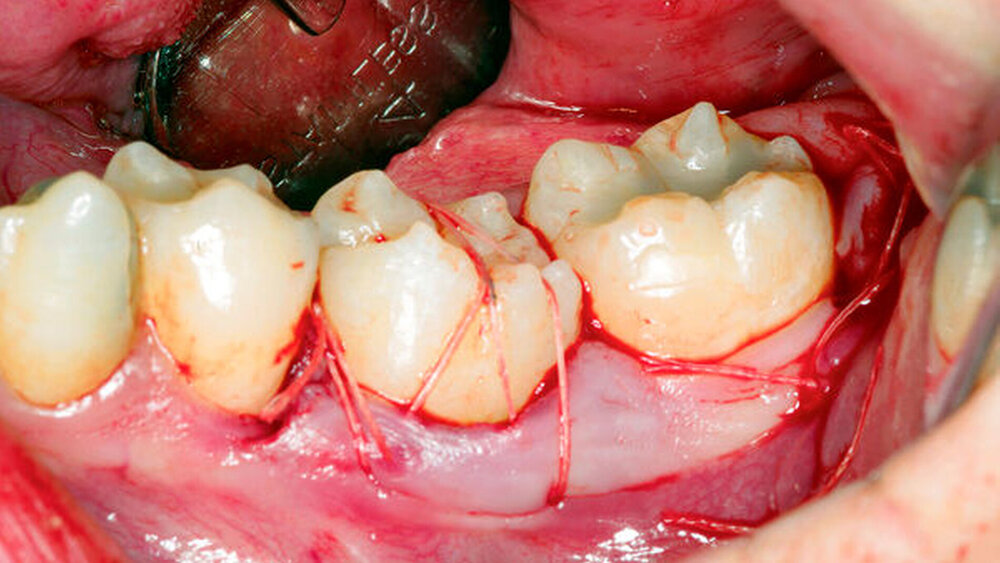

Optimal für eine Autotransplantation sind Zähne mit einem nicht abgeschlossenen Wurzelwachstum (2/3 Wurzellänge), wobei auch Zähne mit abgeschlossenem Wurzelwachstum verwendet werden können. Des Weiteren sollte der zu transplantierende Zahn atraumatisch entfernt und vorsichtig – bei einer möglichst kurzen extraoralen Zeit – behandelt werden, um eine übermäßige Beschädigung der PDL-Fasern zu vermeiden. Die Empfängerstelle muss auf die Größe des zu empfangenden Zahnes aufbereitet werden, was die Entfernung von inter-alveolären Septen beinhalten kann. Die alveoläre Knochenbreite der Empfängerstelle sollte ebenfalls in Bezug auf die Spenderzahnbreite berücksichtigt werden, um sicherzustellen, dass keine übermäßige Belastung oder Resorption auftritt. Wenn 3-D-gedruckte Analoga des Spenderzahns hergestellt werden, kann dies die extraorale Zeit und die Häufigkeit des Einführens des Spenderzahns in die Empfängerstelle minimieren. Nach der Transplantation wird der Zahn flexibel, zum Beispiel über Nähte, für sieben bis zehn Tage stabilisiert, wobei auch lediglich die Friktion an den Nachbarzähnen ausreichend sein kann.